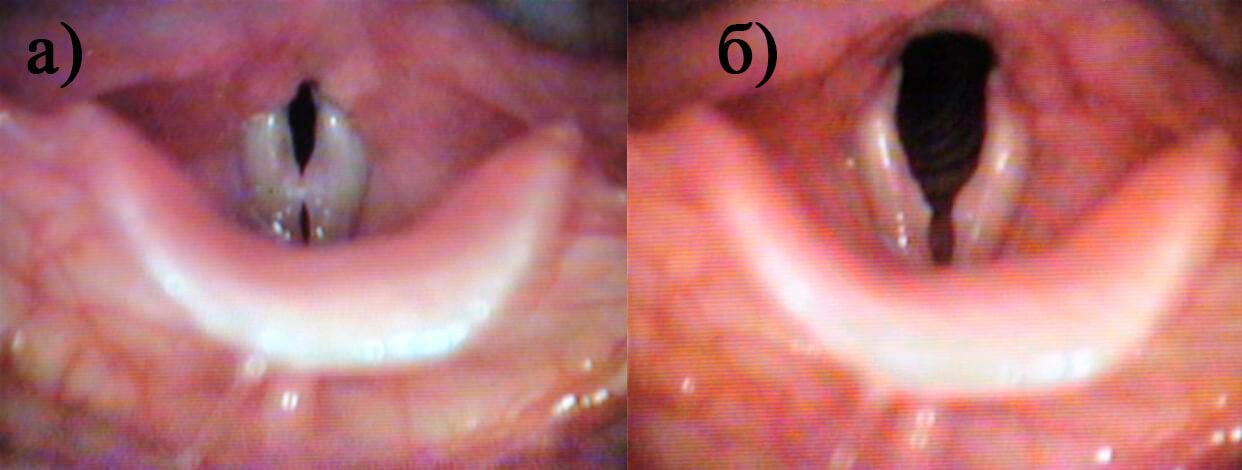

Клинически у 215 (81%) детей были выявлены мягкие узелки на связках, а у 51 (19%) ребенка - жесткие (рис.1).

Фонационная щель имела форму «песочных часов» у 248 (93%) пациентов, овала у 5 (2%), и была широкой линейной у 13 (5%) детей. Две последние формы встретились только у детей с мягкими узелками. В 231 (87%) наблюдении узелки располагались в типичном месте, в узловой точке, на границе передней и средней трети, а в 35 (13%) случаях - в передней трети (рис.2).

Размеры мягких узелков в 103 (39%) случаях соответствовали 1 баллу, в 65 (24%) - 2 баллам, а в 47 (18%) - 3 баллам. Мягкие узелки были такого же цвета, как и остальная поверхность голосовых складок. Напротив, жесткие узелки оказались плотными на вид, а их окраска отличалась от остальной слизистой. Размеры жестких узелков оценивали только в 2 (25%) или 3 (75%) балла. Мягкие узелки в ряде случаев проходили самостоятельно. Об этом свидетельствовали наблюдения за 8 детьми предмутационного периода, у которых мягкие узелки не определялись с наступлением мутации. Другие 12 пациентов с аналогичным диагнозом продолжали заниматься пением и не лечились, что привело к трансформации мягких узелков в жесткие узелки.